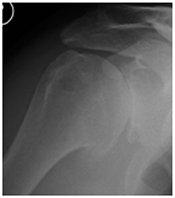

Arthritis of the shoulder shoulder arthritis

X-ray of shoulder demonstrating the arthritis of shoulder